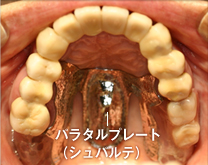

コーヌステレスコープで対応した上顎の入れ歯

外すときは、入れ歯に指がかかるくぼみを持ち上げます。コーヌステレスコープは土台の歯の条件が良い場合に適応します。

残っている歯の本数や場所によっては、禁忌症もあります。